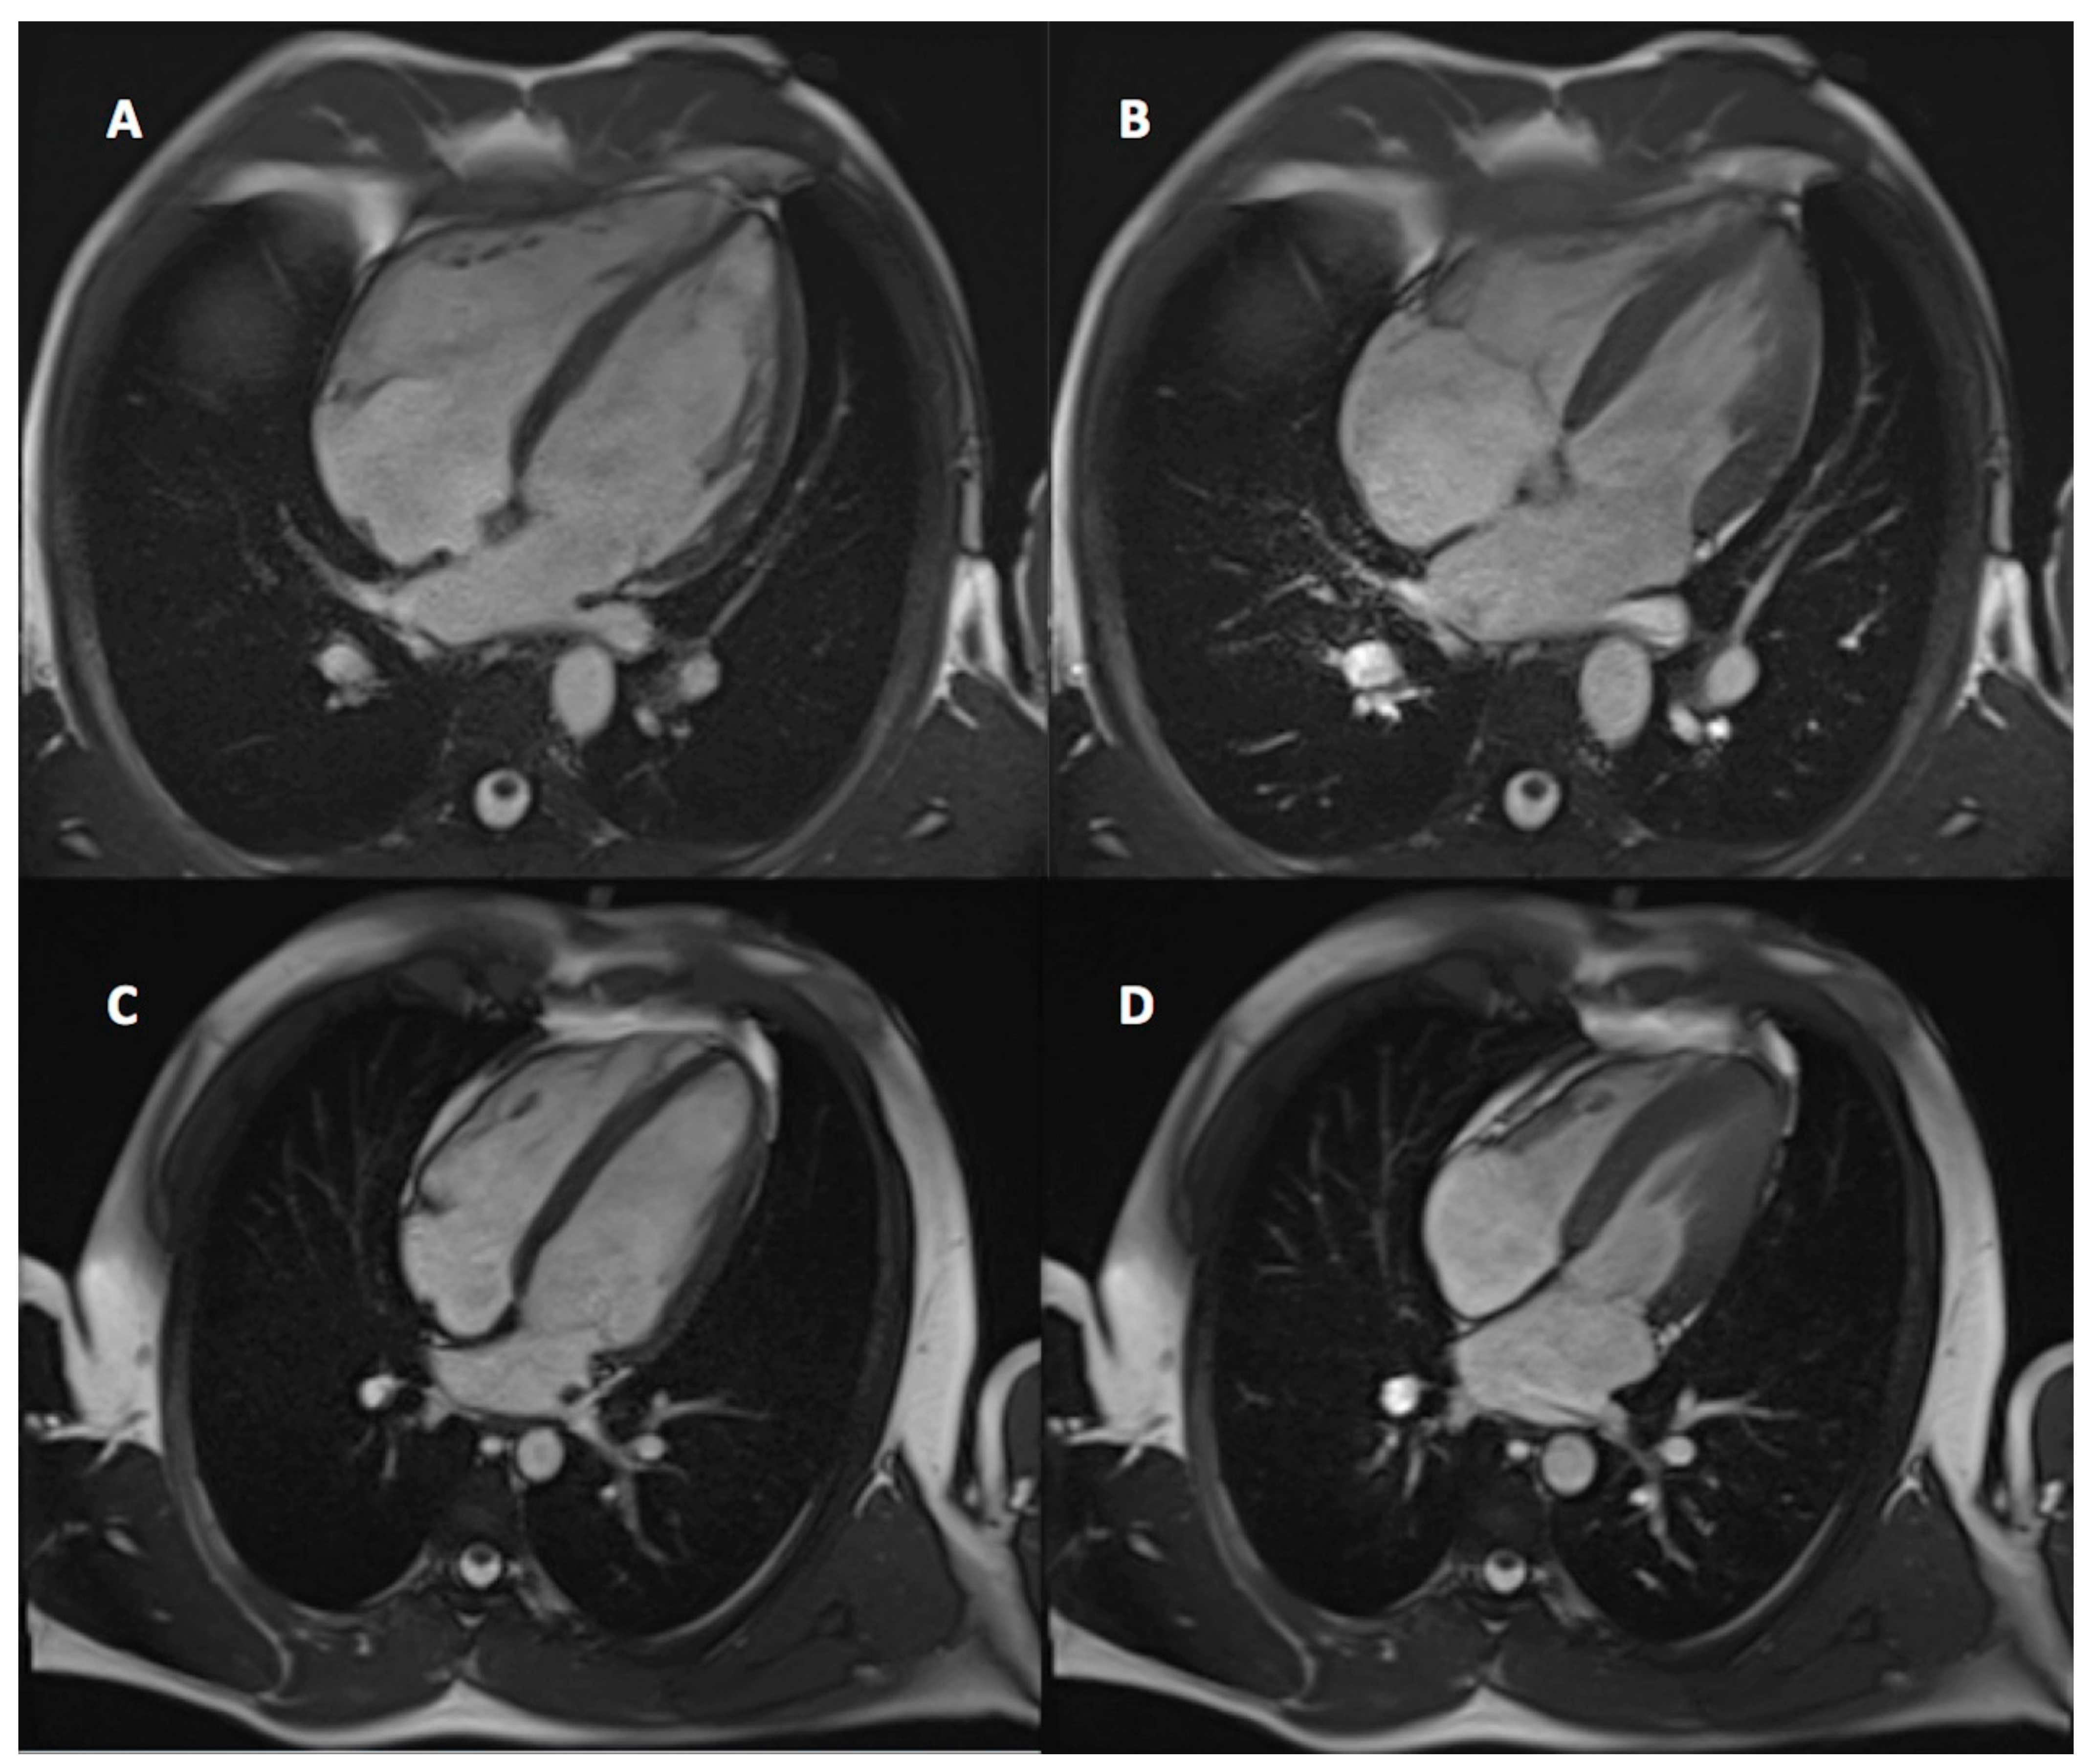

3.2. CMR Findings

3.3. Athlete’s Heart and CMR Result